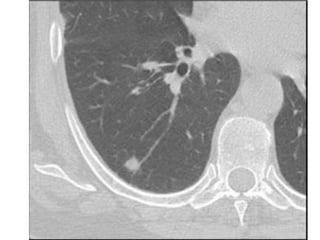

Nódulo pulmonar 8-30 mm

Seguimiento con TAC

3-6-9-12-18-24 meses

Cirugía

videotorascoscópica

Biopsia por congelación

Resección

PET, TC con Cte,

PAAF guiada por TC,

Broncoscopia

- +

Individualizar

opciones no

N Engl J Med 2003;348:2535-42.

ENFOQUE PARA PACIENTES CON NPS

Nódulo pulmonar 8-30mm Calcificación benigna Estabilidad por 2 años sí No mayor evaluación no Riesgo quirúgico aceptable sí Riesgo de cáncer bajo (<10%) Riesgo de cáncer intermedio (10-60%) Riesgo de cáncer alto (>60%) Seguimiento con TAC 3-6-9-12-18-24 meses Cirugía videotorascoscópica Biopsia por congelación Resección PET, TC con Cte, PAAF guiada por TC, Broncoscopia - + Individualizar opciones no N Engl J Med 2003;348:2535-42. ENFOQUE PARA PACIENTES CON NPS